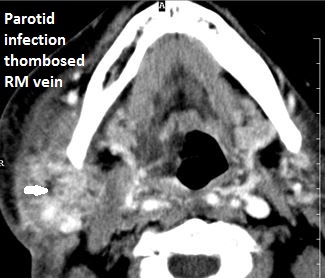

There is a developing abscess within the parotid gland.

There is edema (cellulitis) and/or abscess within the fat surrounding the parotid gland and/or of the masticator space or other adjacent spaces.

The retromandibular and the facial veins are abnormal.